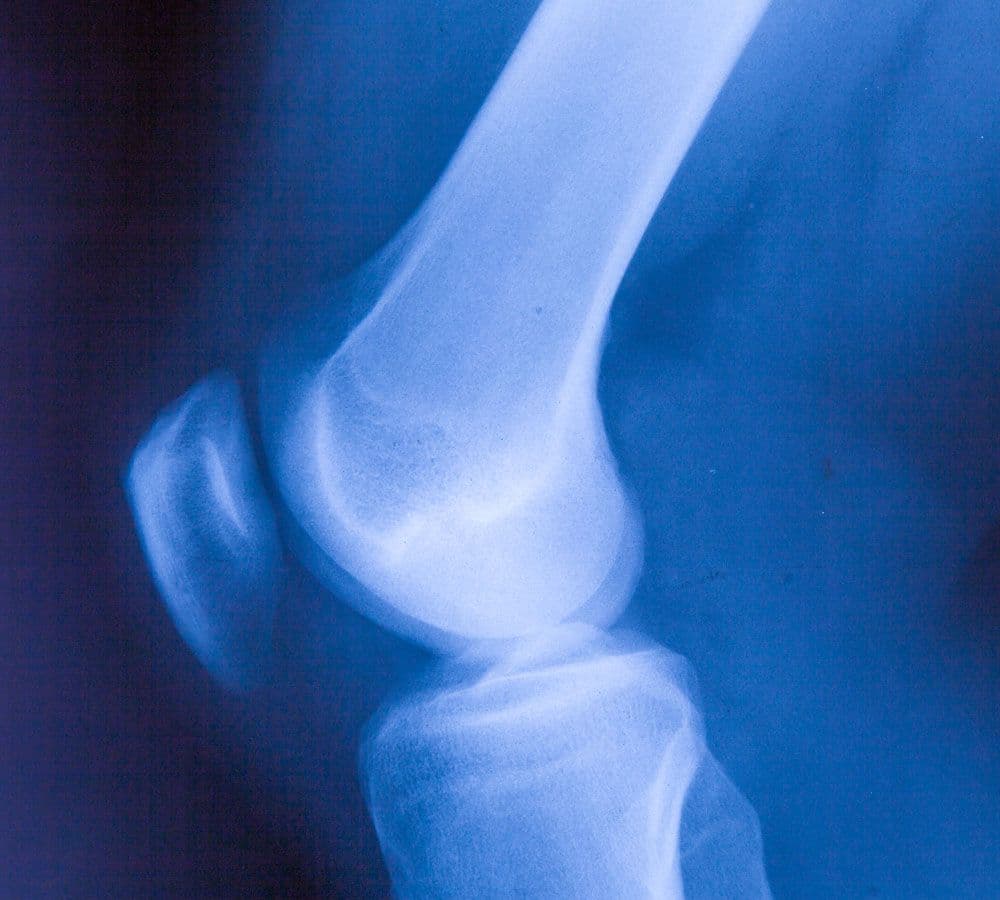

Aby zrozumieć istotę problemu, warto poznać budowę kolana. Więzadło rzepki to mocne, włókniste pasmo łączące dolny biegun rzepki z kością piszczelową. Jego zadaniem jest przenoszenie ogromnych sił generowanych przez mięsień czworogłowy uda, co umożliwia prostowanie kolana, a co za tym idzie – chodzenie, bieganie, wstawanie z krzesła czy właśnie skakanie.

Podstawą diagnozy kolana skoczka jest szczegółowy wywiad oraz precyzyjne badanie fizykalne przeprowadzone przez lekarza lub fizjoterapeutę. Specjalista ocenia lokalizację bólu, tkliwość palpacyjną więzadła, siłę mięśniową oraz wzorce ruchowe. Badaniem obrazowym z wyboru jest USG, które pozwala ocenić strukturę więzadła, jego grubość, obecność zmian degeneracyjnych oraz stan zapalny. W przypadkach wątpliwych lub przed planowanym leczeniem operacyjnym zleca się rezonans magnetyczny (MRI).